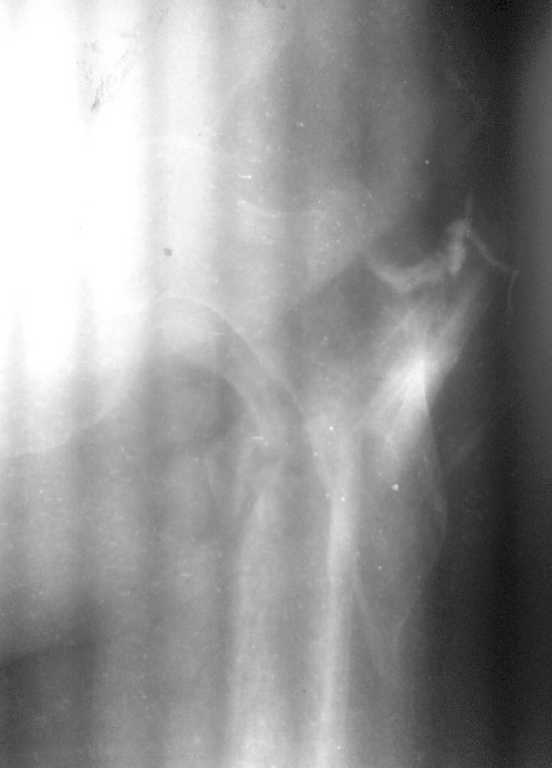

Фистула функционирует от случая к случаю - последние 2 дня выделений небыло, сделали контрастирование (с трудом вошло 5 мл контраста). Признаков воспаления в зоне поражения нет, лабораторные показатели в пределах нормы. Судя по распростарнению контраста - локальный остеомиелит в месте расположения стержня АВФ

Dr Alex, добрый день. Я за двухэтапное лечение, если есть проблемы с АВФ(нежелание больной или докторов)как вариант наложить ДСВ, 2 спицы через бугристость ББК, груз 10% от массы больной, иссечь гнойный очаг и подержать до заживления.Рентген-контроль на ДСВ, если удалось растянуть по длине, то идти на закрытый синтез. Не могу разглядеть на снимках "ушел" малый вертел или нет? Если перелом из чрез-под-вертельных, то надо брать длинный гамма-гвоздь. Без ЭОПа, будет .опа, но очень интересно, 2 рентген-аппарата, лаборант бегает матерится, шейка спицами маркируется, ах молодость-молодость, приятно вспомнить.

Малый вертел с небольшим фрагментом кортикала отломан.